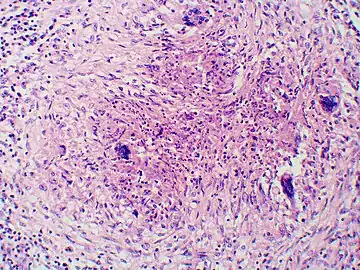

Once suspected, the diagnosis of blastomycosis can usually be confirmed by demonstration of the characteristic broad based budding organisms in sputum or tissues by KOH prep, cytology, or histology.[27] Tissue biopsy of skin or other organs may be required in order to diagnose extra-pulmonary disease. Blastomycosis is histologically associated with granulomatous nodules.

Inhaled conidia of Blastomyces are phagocytosed by neutrophils and macrophages in alveoli. Some of these escape phagocytosis and transform into yeast phase rapidly. Having thick walls, these are resistant to phagocytosis. Once they have transitioned to the yeast phase, the Blastomyces cells express the protein BAD-1, which helps the yeast cells attach to host cells, and also impairs activation of immune cells while inhibiting release of tumor necrosis factor. [23] In lung tissue, the cells multiply and may also disseminate through blood and lymphatics to other organs, including the skin, bone, genitourinary tract, and brain. The incubation period for pulmonary blastomycosis is 3 to 15 weeks, although 3050% of infections are asymptomatic.[24]